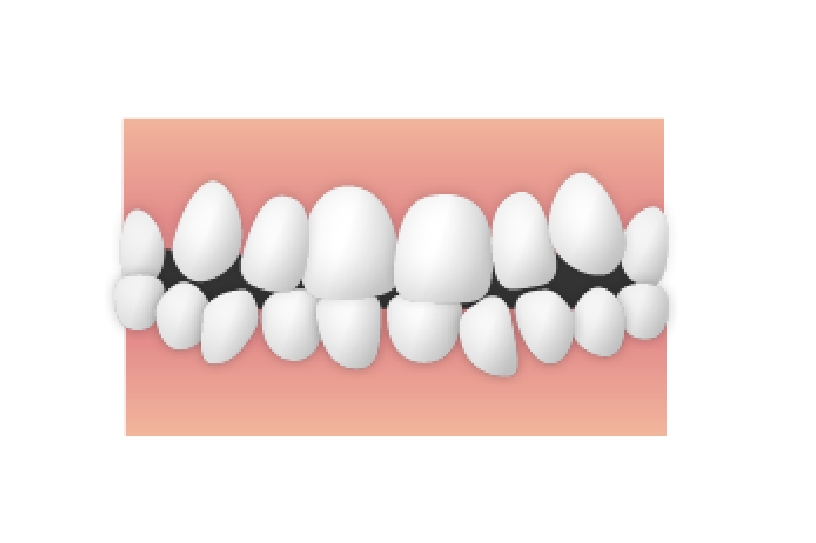

開咬(かいこう)

開咬

奥歯がかみ合わさった状態であるにもかかわらず、前歯の部分が閉じていない症例です。このケースでも、異常嚥下癖(本人は気付いていません・・・)が大きく関係してきます。食べ物を飲み込むときに、舌の逃げ場がないので、前歯を押し広げてしまうのです。治療に際しては、移動した歯を元の場所に戻すことが目的となります。